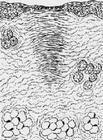

肉芽組織增生和瘢痕形成 大約從第3天開始從傷口底部及邊緣長出肉芽組織,填平傷口。毛細血管大約以每日延長0.1~0.6mm的速度增長,其方向大都垂直於創面,並呈袢狀彎曲。肉芽組織中沒有神經,故無感覺。第5~6天起纖維母細胞產生膠原纖維,其後一周膠原纖維形成甚為活躍,以後逐漸緩慢下來。隨著膠原纖維越來越多,出現瘢痕形成過程,大約在傷後一個月瘢痕完全形成。可能由於局部張力的作用,瘢痕中的膠原纖維最終與皮膚表面平行。